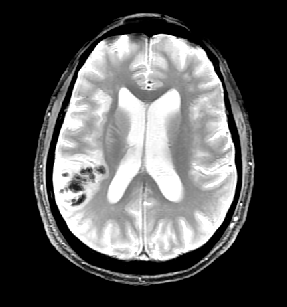

L'acquisition des images a été réalisée lors du séjour du patient en ré-éducation, 6 mois après l'apparition des symptômes. Les séquences permettent de mettre en évidence un AIC carotidien droit au stade chronique (hyposignal en pondération T1 et hypersignal en pondération T2) avec atrophie du tissu cérébral de l'hémisphère droit. L'angiographie-IRM (ARM) des vaisseaux du cou montre une dissection de l’artère carotide interne droite (aspect en flamme de bougie) avec retentissement hémodynamique d’aval.

Coupe axiale, pondération T2 |

- IRMsujet12211anatpathologieAVC_T2.img : Image acquise en pondération T2. Cette image est utilisable uniquement dans le plan axial du fait d'un trop faible nombre de coupes dans les autres plans. Caractéristiques techniques : FOV : 512, 46 coupes ; résolution spatiale : 0,47 X 0,47 X 3mm3 ; TR : 4500ms ; TE : 86ms ; Flip angle : 90°